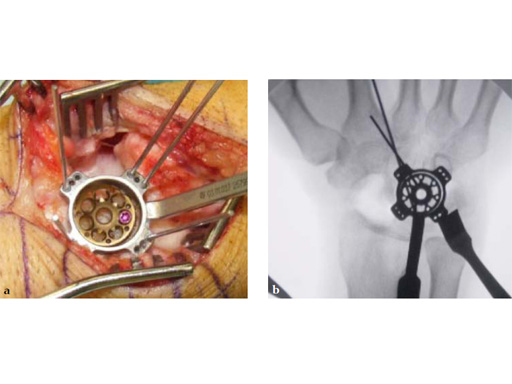

Fig 5ab Plate positioning and fixation. The combined VA-locking-standard guide allows drilling in the appropriate direction.

Fig 5cd Plate positioning and fixation. The combined VA-locking-standard guide allows drilling in the appropriate direction.